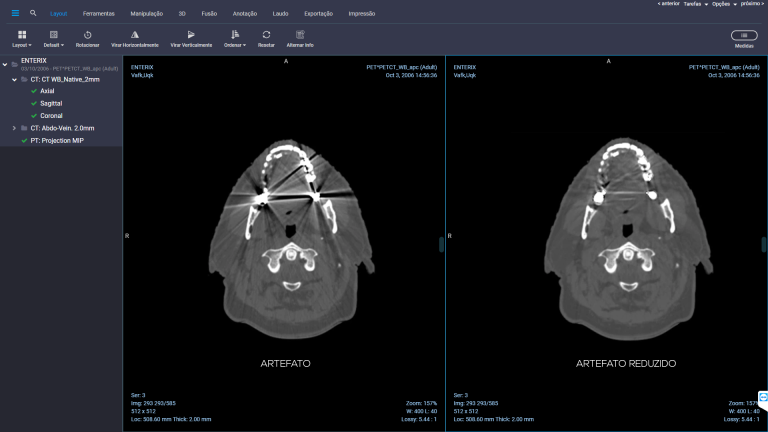

A startup RT MEDICAL SYSTEMS desenvolveu um software capaz de reduzir ruídos em imagens de tomografia computadorizada e PET/CT causados por objetos de metal, como implantes ortopédicos e obturações dentárias. Esses artefatos se exibem como listras e áreas escuras nas imagens, impossibilitando o diagnóstico e dificultando a realização de contornos de estruturas e volumes alvo por exemplo no planejamento de radioterapia.

O sistema desenvolvido pela RT MEDICAL SYSTEMS, melhora a qualidade da imagem e a visualização anatômica, reduzindo o efeito do metal nas imagens. Isso ajuda a acelerar o fluxo de trabalho dos médicos, possibilitando laudos mais rápidos e a redução do tempo do planejamento radioterápico quando implantes ortopédicos estão presentes.